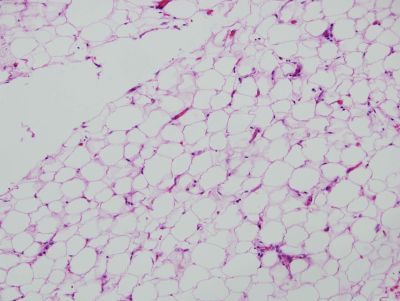

Adipose tissue - histology slide

Histology slide of adipose cells in the tissue surrounding an artery. 200X magnification.